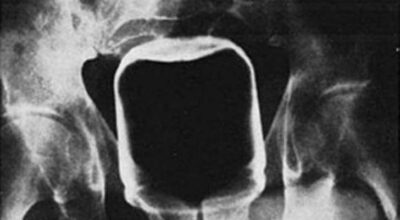

Esta recopilación de imágenes recoge alguna de las situaciones más estrambóticas que se han podido dar en una sala de rayos X. Todas ellas tienen algo en común: Son objetos extraños para el cuerpo humano que, de alguna manera han encontrado una vía de entrada, pero se han perdido a la hora de encontrar la de salida.

Muñecas de juguete descabezadas, botellas, armas, frascos, botes de plástico, teléfonos y hasta una cinta de casete pueden encontrarse en esa suerte de “punto limpio” al que ha quedado reducido el interior de los afectados.